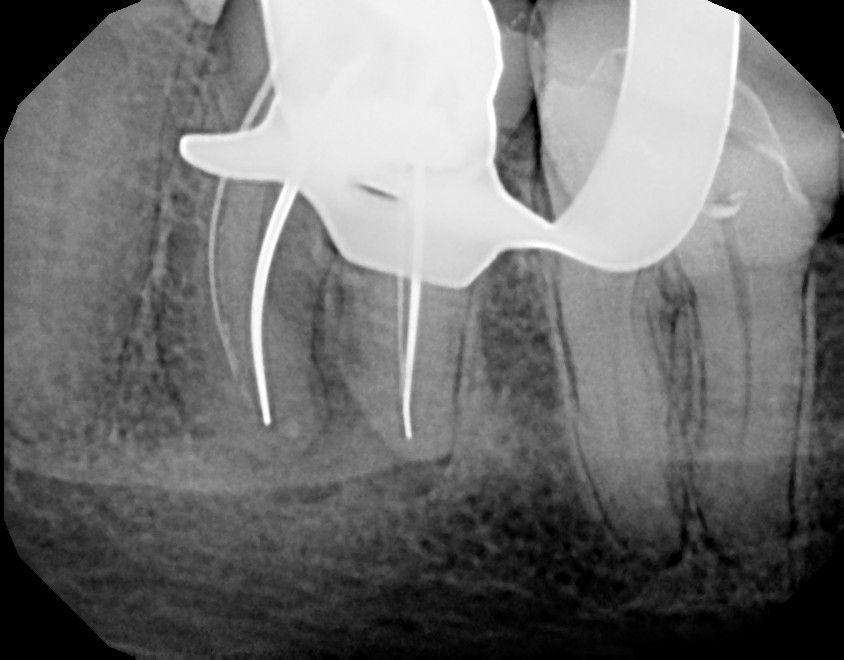

Silver points (Cones) can be tricky, especially when you can't get a good grip to pull them out or if they break. Retreatments are tedious work and almost always require more time and patience, but they provide a satisfaction that conventional root canal treatment doesn't offer when everything goes well!